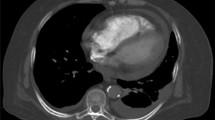

The segmentation of the embolus and pulmonary trunk was performed in each patient using the interactive segmentation algorithm GrowCut [10,11,12]. An example of the segmentation is shown in Fig. 2. The segmentation in each case was evaluated by two experienced radiologist (V.K. and S.S.M., board-certified radiologists with four and seven years of experience in experimental imaging, respectively).

Exemplary segmentation of the pulmonary arteries and the embolus. A, Unsegmented axial slice; B, Segmented axial slice; C, Unsegmented coronal slice; D, Segmented coronal slice; E, Unsegmented sagittal slice; F, Segmented sagittal slice; G, Final segmentation of the embolus. Abbreviations PE, pulmonary embolism

In case of any disagreement with the initial segmentation, the process was repeated, and necessary adjustments were made. All radiologists participating in the assessment were kept entirely unaware of the clinical data pertaining to the patients.